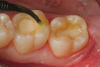

A 66 year-old female patientpresented with a "stained" occlusal groove in tooth No. 13 that did not "stick" with an explorer tip (Figure 1).  Upon radiographic examination (Figure 2), a rather large carious lesion was discovered that encroached upon the dental pulp.  There were no other clinical or subjective signs to alert the clinician or patient to the extent of the damage that had already occurred in the tooth. Figure 3 through Figure 5 show selective caries removal using a round end plastic polymer bur (SmartBurII, SS White).  Before caries removal, isolation of the operative quadrant was achieved using Isovac (Zyris). Because of its Knoop hardness of 90, SmartBurII allows for removal of infected dentin only, while allowing affected dentin to remain for potential remineralization with a bioactive liner or base material.

Fig. 2. A radiographic view of the extensive carious lesion on the distal of tooth No. 13.

Figure 2